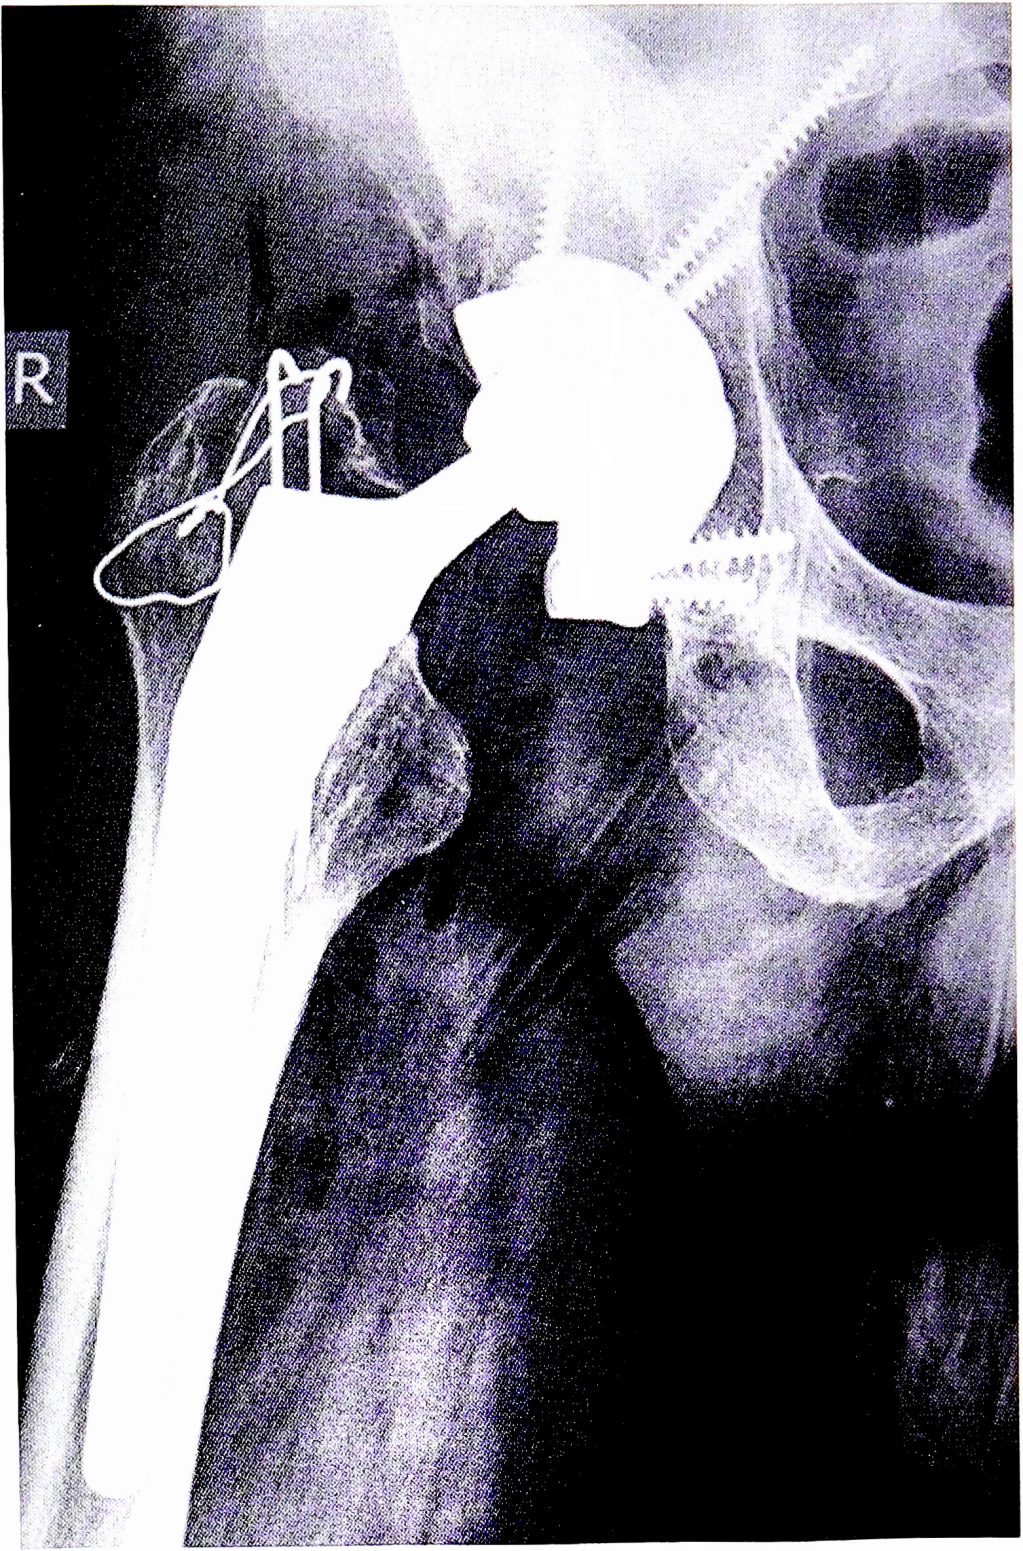

Рис. 5. Интраоперационный перипротезный перелом А3. Отрыв большого вертела. Фиксация вертельной пластиной (https:// medapparatus.com/Gallery/Gallery_JointArthroplasty_Page4.html).

Fig. 5. Intraoperative periprosthetic fracture A3. Greater trochanter avulsion. Fixation with the trochanteric plate.